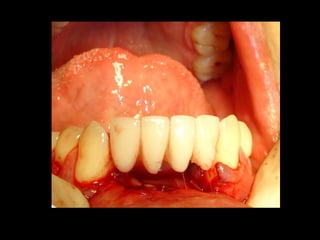

Trismus importante debido a que

El tumor ya rompió el hueso com-

Pacto de la cara interna de la

Mandíbula y empezó a tomar el

Músculo pterigoideo interno y

milohioideo.

Luxación de hemimandíbula

Pieza quirúrgica

Plantilla flexible para dar forma previa al implante

Se respetó el cóndilo para anclar la prótesisSe respetó el cóndilo para anclar la prótesis

Límite tumoralLímite tumoral

Area de lisis ósea a nivel de la línea

Miliodes que contracturó los músculos

Milohioideo y pterigoideo interno

Dificultando la deglución y determinando

Trismus importante.

Pieza en proceso de examen por histopatología

Dr. Ismael Espejo Plascencia Patólogo

48 horas de post-operatorio